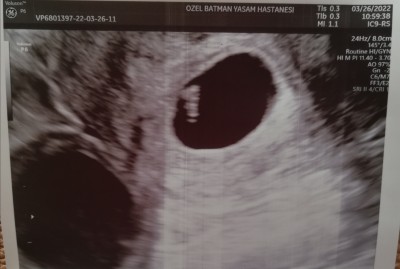

:(Arkadaşlar son adet tarihim 4 şubat. Ona göre 7 haftalık hamileyim. Doktora bebeğin kalp atışı için gittim ama üstten baktı göremedi alttan baktı bebek var ama kalp atışı yok dedi. Bir hafta sonra yine gel bakalım dedi. Çok moralim. Bozuldu ultrason fotoğrafı Ekliyorum lütfen bakın dua edin. Önceki bebeğim de önceki kalp atışı duyulacakti ki düşük oldu yine korkuyorum ☹️☹️☹️ Başına böyle gelen oldu mu ne yapmalıyım ağlamak istiyorum ☹️ bide 10 gün önceki beta 10279 idi 10 gün sonra 27400 civarı doktor az dedi. Yaa off yaa yine üzülmek istemiyorum ☹️

7 haftalık iken alttan görülmedi mi. Bide ultrasonda bebeği ölçtü 5.23 mm dedi altında 6 haftalık diyo ama uygulama göre 7 haftalık hamileyim niye böyle ki